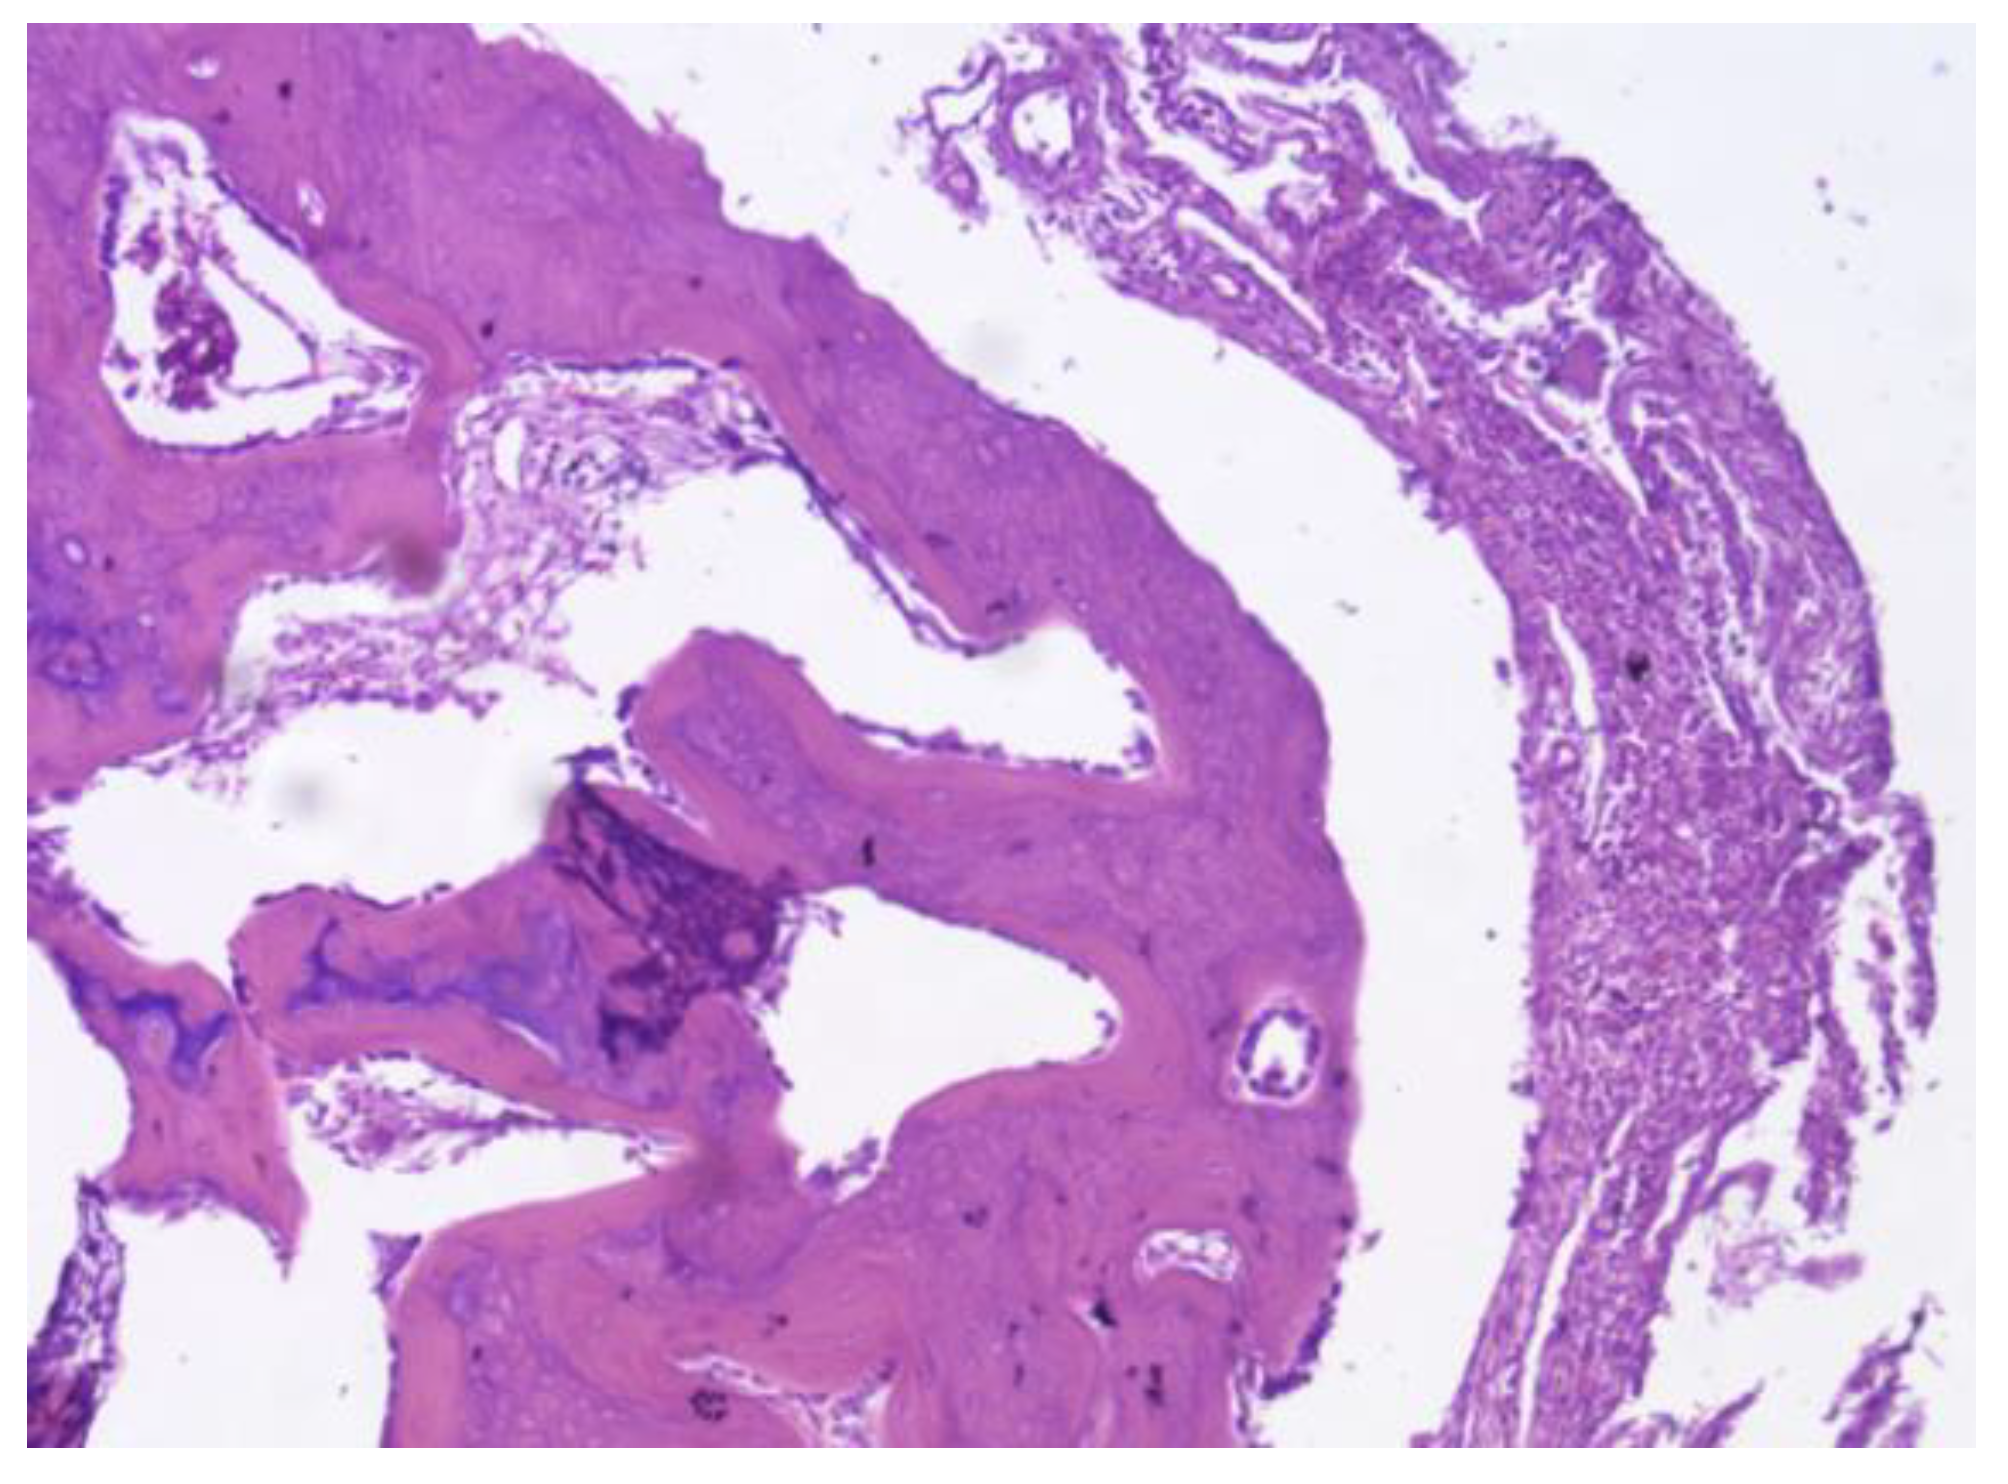

Figure 31. No osteoid formation or synovial metaplasia was identified, indicating the absence of abnormal bone matrix deposition or undesirable cellular transformation.

PEEK: The histological samples obtained at both the third and fourth months revealed a predominantly fibrointegrative response, characterised by the presence of a mature fibrous capsule encasing the implant. Cortical bone was observed in direct contact with the prosthesis, accompanied by areas of mature periprosthetic fibrosis, suggesting a degree of mechanical stability and material anchorage. The fibrotic reaction was moderate, with mild inflammatory infiltrates and limited neovascularisation, all of which reflect a favourable biocompatibility profile. Notably, no osteoid formation or synovial metaplasia was identified, indicating the absence of abnormal bone matrix deposition or undesirable cellular transformation. These findings suggest that PEEK elicits a stable yet primarily fibrous integration rather than a true osteointegration. (Figure 31)

Figure 33. PLDLLA histological analysis shows cortical bone in close apposition to the prosthesis, accompanied by mature periprosthetic fibrosis.

PLDLLA: Histological post-implantation analysis at both the third and fourth months revealed cortical bone in close apposition to the prosthesis, accompanied by mature periprosthetic fibrosis. Effective osteointegration was evident, indicating that the material achieved direct bone contact without the interposition of fibrous tissue a key indicator of stable mechanical and biological integration. The periprosthetic fibrosis and inflammatory response were both mild, with minimal cellular infiltration, reflecting excellent biocompatibility. Scattered neovascularisation was present, supporting ongoing tissue remodelling. Importantly, there were no signs of synovial metaplasia or osteoid formation, further confirming the absence of pathological tissue reactions. Overall, these findings support a stable and successful osseous integration of the PLDLLA implant. (Figure 33)